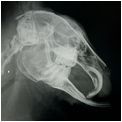

Das digitale Zahnröntgen, auch bei Nagern, erlaubt uns eine genaue Beurteilung der Zahnwurzeln, da diese oft Verursacher vieler Erkrankungen sein können